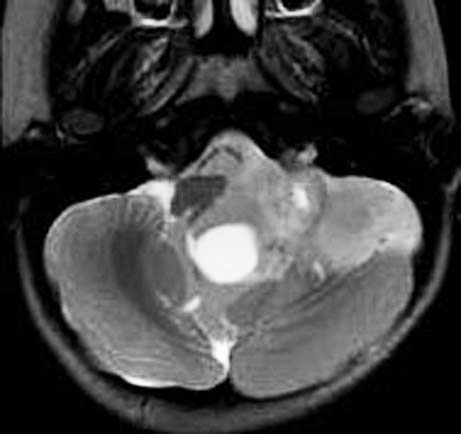

青年に発生したものです。かなり分化度の高い延髄背側 ovex 発生の上衣腫です。境界が明瞭なのですが,実際に側方(延髄小脳脚槽)で椎骨動脈や後下小脳動脈,下位脳神経に癒着しているので剥離は必ずしも容易ではありません。この例では幸い全摘出できました。

- MRIでみると脊髄の真ん中にあるのが特徴です

- ガドリニウム造影剤で増強されて白く写ります